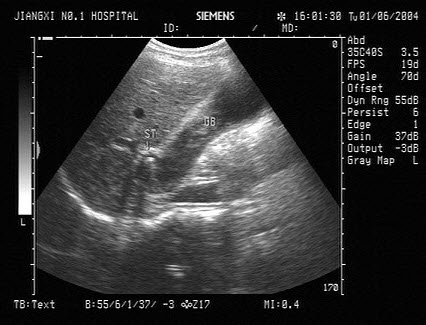

11、单项选择题

某患者阴囊增大,自诉用力时阴囊可增大,平卧缩小,无外伤史。B超检查超声声像图如下,最可能的诊断为()

A.鞘膜积液

B.附睾炎性包块

C.斜疝

D.附睾结核

E.股疝